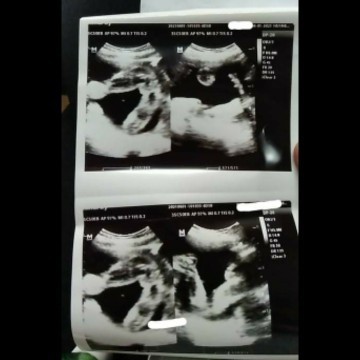

sa tingin nyo po mga momsh ano gender ng baby ko hehe 🤗